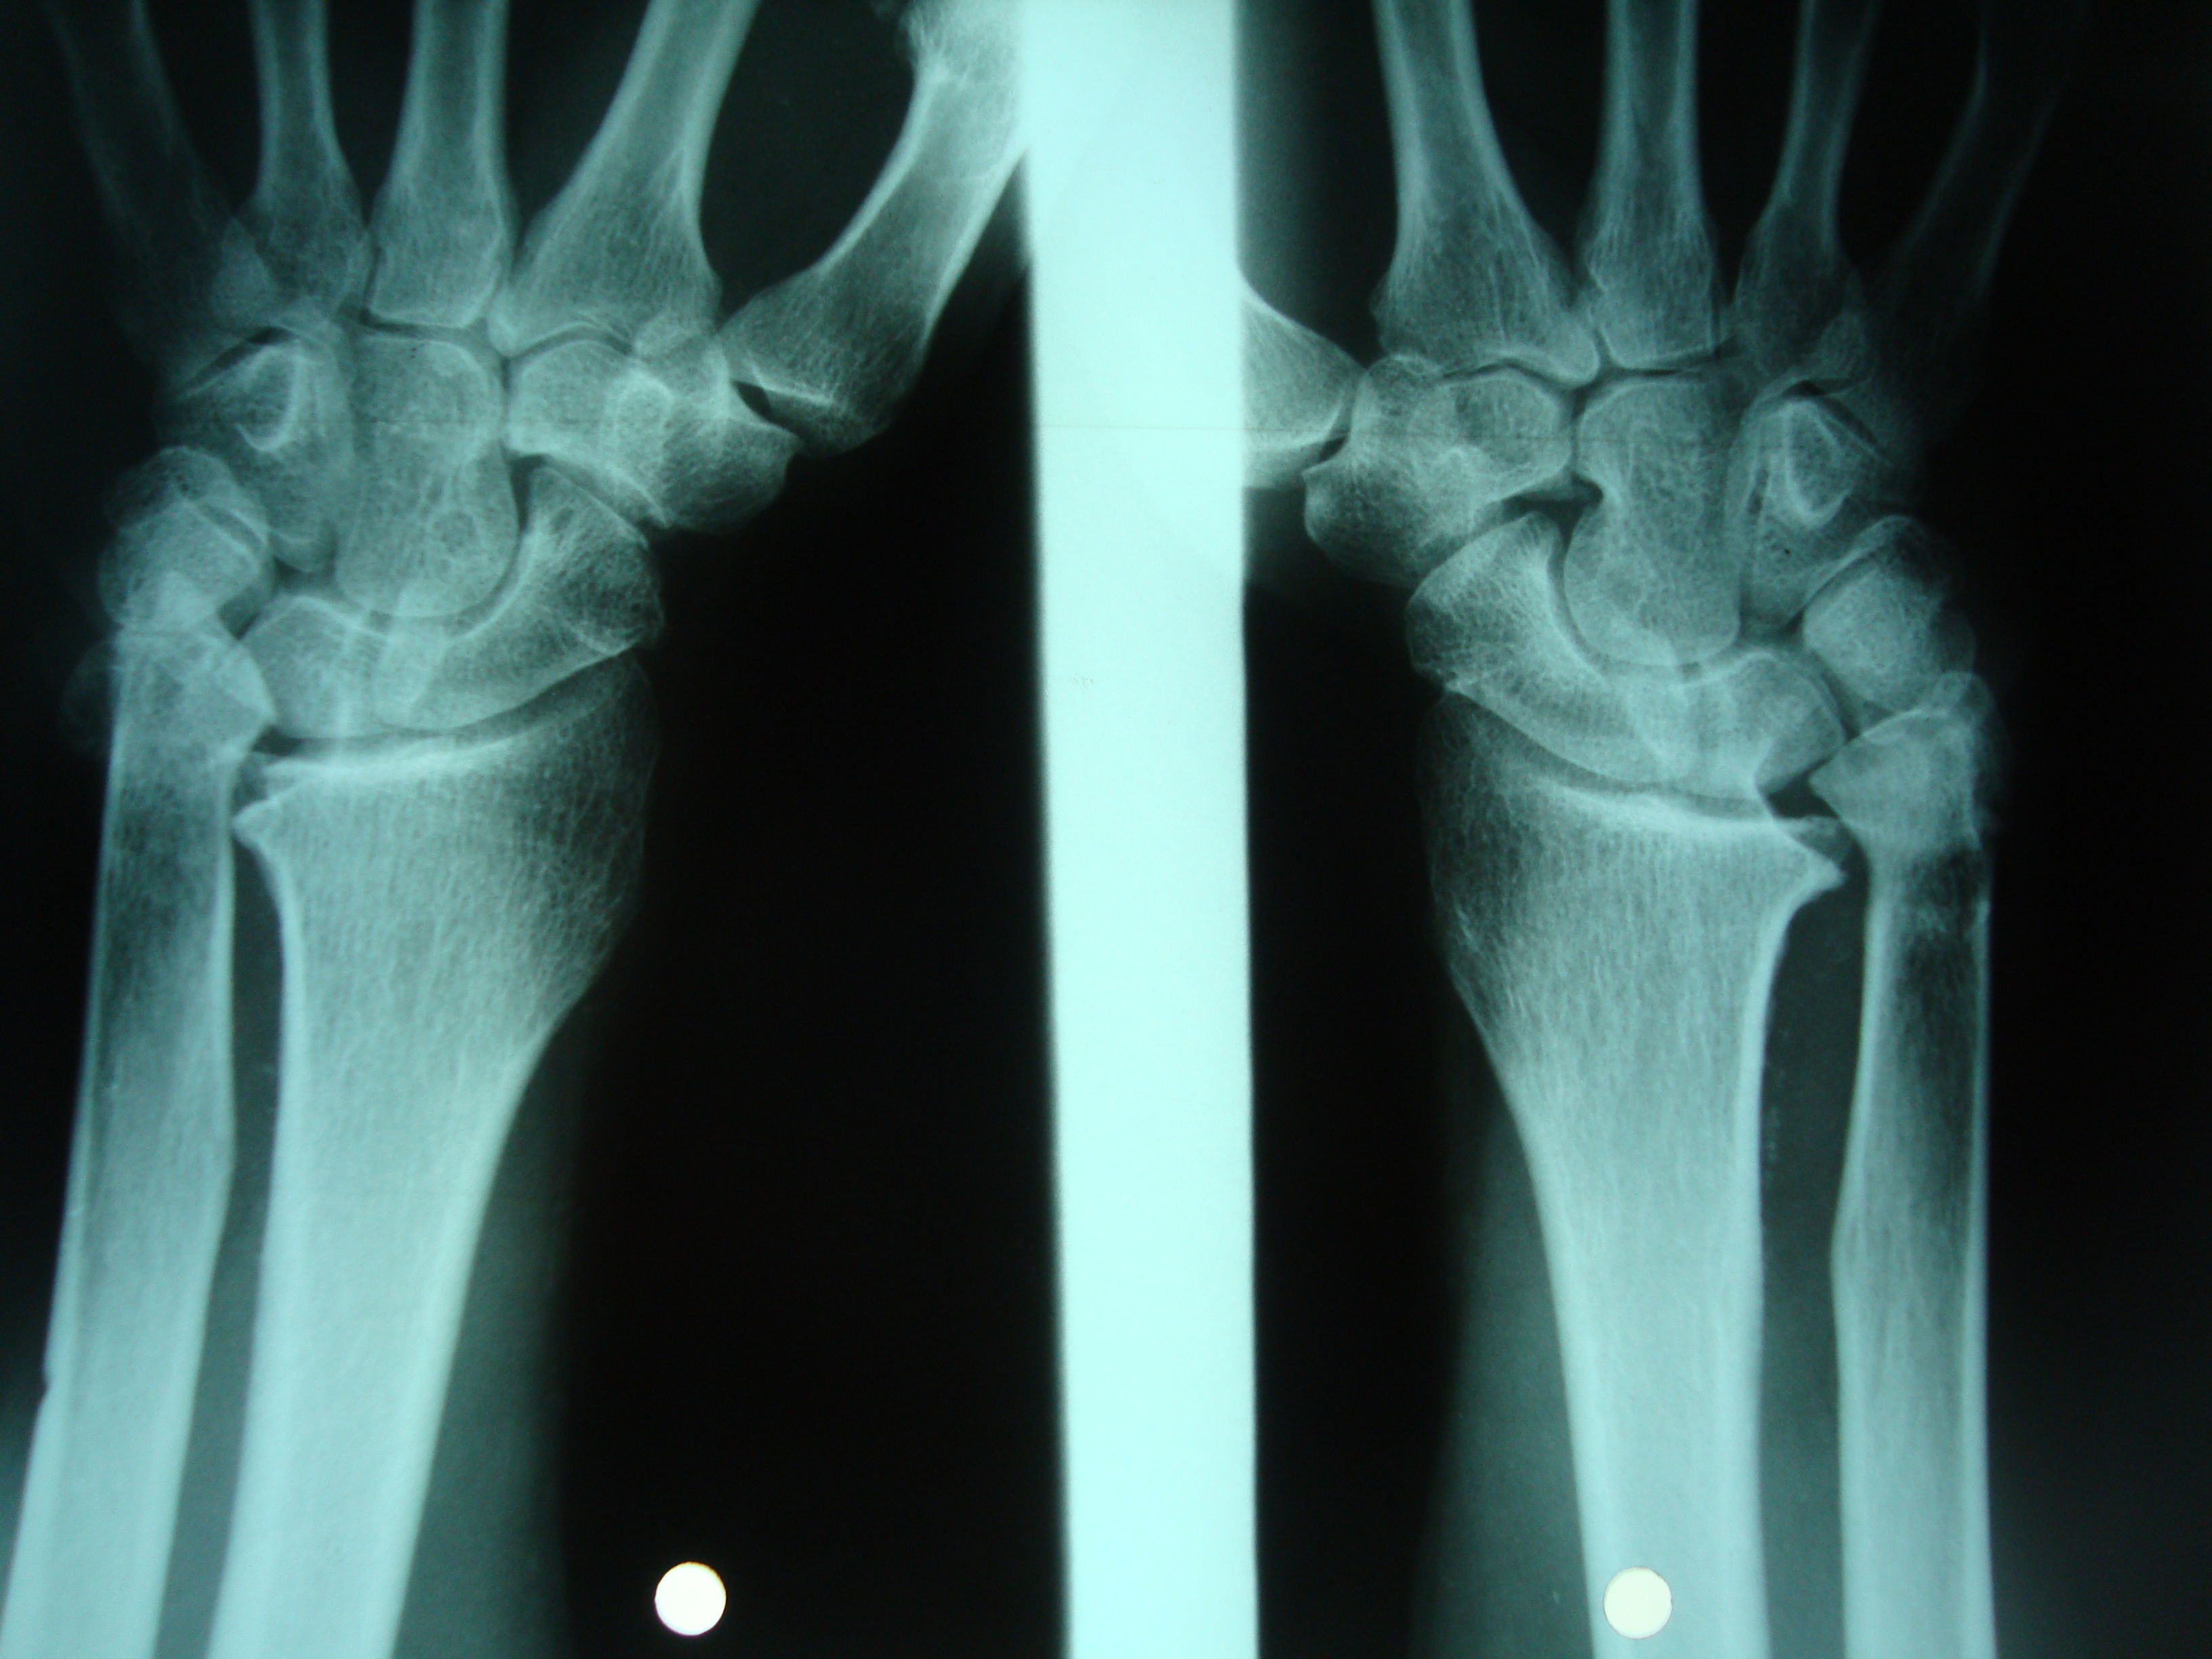

Rotura de los tendones extensores de los dedos por cúbito plus idiopático bilateral. Informe de un caso.